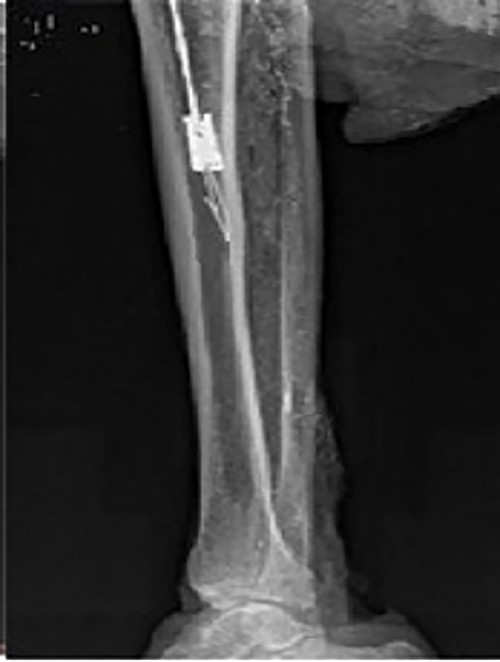

Intraoperative X-ray showing that the broken nail extractor was pulled back and the barb hooked the canal wall.

For the removal procedure, we made a hole at the entry point of the tibia for the intramedullary nail, inserted the guide needle and reamed the tibial medullary cavity with a Φ 11 mm drill bit along the guide needle (Fig. 3). The residue was flushed and aspirated after reaming. We adjusted the diameter of the barb on the spear of the homemade minimally invasive broken nail extractor to 3 mm, then inserted it into the medullary cavity and passed the nail extractor through the canal of the broken nail (Fig. 4). When the extractor was pulled back, the barb hooked the canal wall (Fig. 5) and successfully extracted the broken nail (Fig. 6). The operation was performed under fluoroscopy.